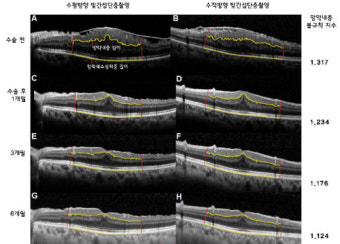

OCT 검사는 망막전막증 진단에 있어서 가장 핵심적인 도구입니다. 광간섭단층촬영(Optical Coherence Tomography)은 망막의 단면을 고해상도로 촬영하여, 눈으로는 볼 수 없는 세밀한 구조까지 시각화할 수 있게 해줍니다.

이 검사는 마치 CT 촬영처럼 망막을 층별로 잘라보는 것과 같아, 망막 위에 형성된 막의 두께, 위치, 망막층의 변형 여부 등을 정밀하게 확인할 수 있습니다. OCT 영상에서 망막전막이 보이는 경우, 얇은 막이 망막 위에 덮여 있고 주변을 잡아당기는 형태로 나타나며, 심한 경우 망막이 주름지거나 부풀어 오르는 양상도 관찰됩니다.

OCT는 통증이 전혀 없고 몇 초 만에 끝나는 비접촉식 검사로, 환자의 부담이 거의 없습니다. 또한 경과 관찰에도 매우 유용하여, 시간이 지남에 따라 막의 변화나 망막 상태의 호전/악화를 비교 분석할 수 있습니다.

망막전막증은 겉보기로는 증상이 미미할 수 있으나, OCT를 통해 내부 구조 변형이 진행되고 있다는 사실이 밝혀지는 경우가 많습니다. 특히 수술 여부를 판단하거나 수술 후 회복 상태를 확인할 때 이 검사는 없어서는 안 될 중요한 진단 도구입니다.